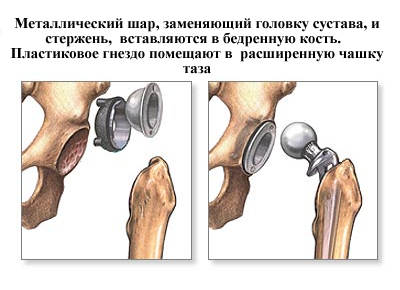

Тотальное эндопротезирование тазобедренного сустава – это операция, когда выполняют удаление поврежденной кости и хряща, с последующей заменой на протез, как головки бедренной кости, так и вертлужной впадины.

Протезы с «бесцементным» типом фиксации покрыты специальным пористым материалом, который позволяет костной ткани пациента по прошествии определенного времени врастать в эти микроскопические поры. Во время операции компоненты эндопротеза – вертлужный компонент (чашка) и бедренный компонент (ножка) впрессовываются в кость для первичной фиксации протеза. Далее, через определенный промежуток времени, костные клетки проникают в специальное пористое покрытие компонентов эндопротеза (кость — это тоже живая ткань), что обеспечивает отличную фиксацию эндопротеза в кости пациента без применения каких-либо дополнительных материалов (без костного цемента).